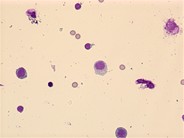

Myeloma: CNS - 1.

Category: Lymphoma: Mature B-cell and Plasma cell Neoplasms > Plasma Cell Neoplasm

Plasma cells and lymphocytes are noted in this CSF cytospin from a patient with CNS involvement by multiple myeloma.